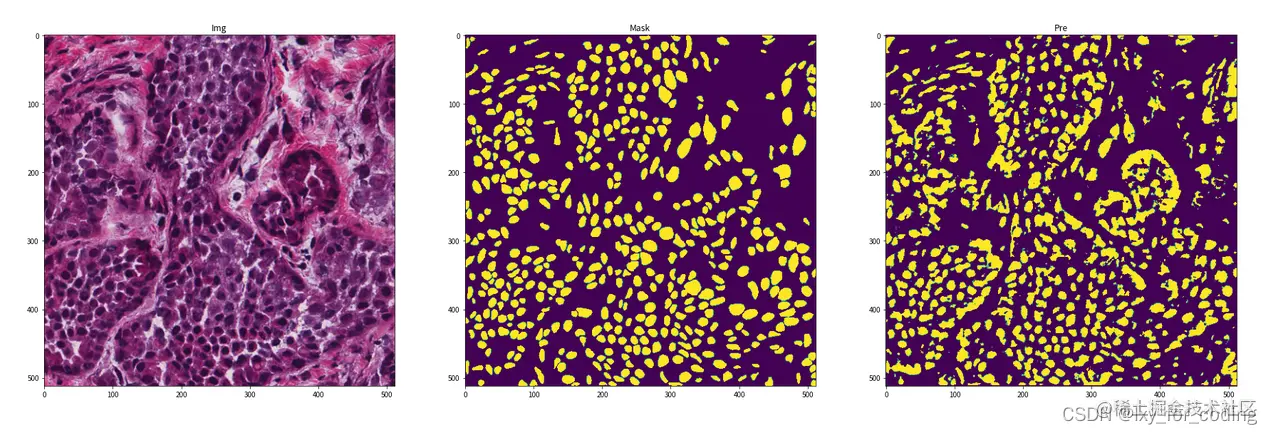

step6:可视化展示

img = img.mul(255).byte().squeeze().numpy().transpose((1, 2, 0))

print("img.shape={}, mask.shape={}, pre.shape={}".format(img.shape, mask.shape, pre.shape))

fig, ax = plt.subplots(1, 3, figsize=(30, 10))

ax[0].imshow(img)

ax[0].set_title('Img')

ax[1].imshow(mask)

ax[1].set_title('Mask')

ax[2].imshow(pre)

ax[2].set_title('Pre')

在这里插入图片描述